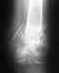

здравствуйте извините что вклинился в ваш разговор просто у меня похожая ситуация.....у меня оскольчатый перелом обеих костей голени мне поставили штифт.Прошло 6 месяцев врачи говорили что всё срастается сегодня отправили на чтение снимков и там мне врач сказал что сращения НЕТ!!!! сказал что нужно убрать винты и ставить Илизарова...ПОДСКАЖИТЕ ПОЖАЛУЙСТА ЧТО МНЕ ДЕЛАТЬ?????